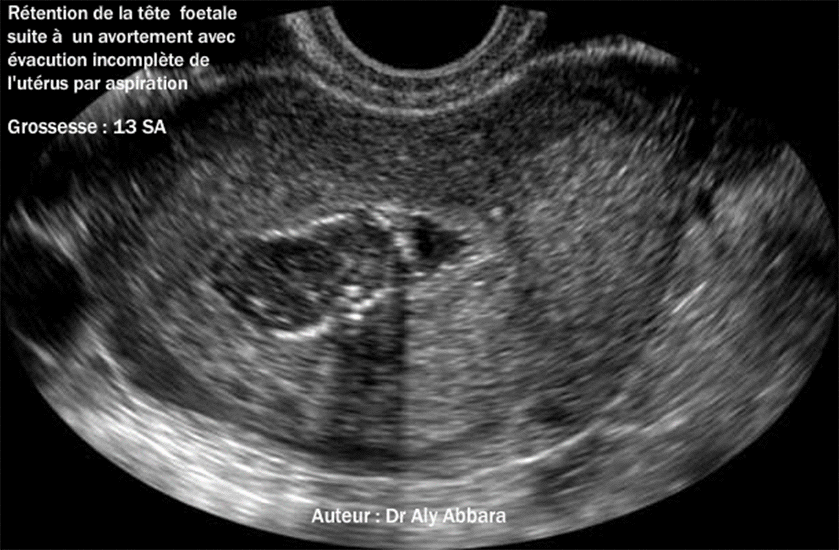

Rétention du pôle céphalique foetal suite à un avortement à 13 SA avec l'évacuation incomplète, par aspiration, des produits de la grossesse contenus dans la cavité de l'utérus. (Le pôle céphalique retenue dans la cavité utérine mesure 26 x 24 x 16 mm de dimensions) |